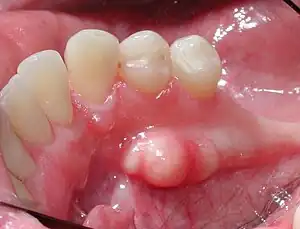

An oral torus - also known as: dental torus - is an oral condition in which bony growth occurs in the mouth; there are three locations in which oral tori may appear: the hard palate (torus palatinus), in the lower jaw underneath the tongue (mandibular torus), and/or on the back or upper gums near the cheeks (buccal exostoses). While the growth is bony and hard at these locations, they are usually harmless and painless, so treatment is not required to treat this condition. However, while usually harmless and painless, oral tori may start to interfere with an individual's speech, swallowing, other functions, or dental procedures (in these circumstances, treatment is necessary).[1][2][3][4]

- one or more bony growths at one or more locations of the mouth (palatines, mandibular, buccal)